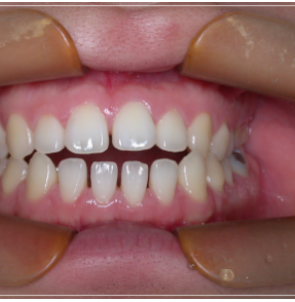

이 처럼 입을 다물어도 어금니만

맞물린 채 앞니가 맞물리지 않는 증상을

개방교합이라고 부르는데요.

개방교합은 입을 다물때 안쪽

어금니만 맞닿고 앞니 쪽은 닿지 않아

입술이 붕 떠 있는 상태를 말했어요.

이처럼 앞니가맞물리지 않고

붕 떠있는 증상이 오랜기간 지속되면